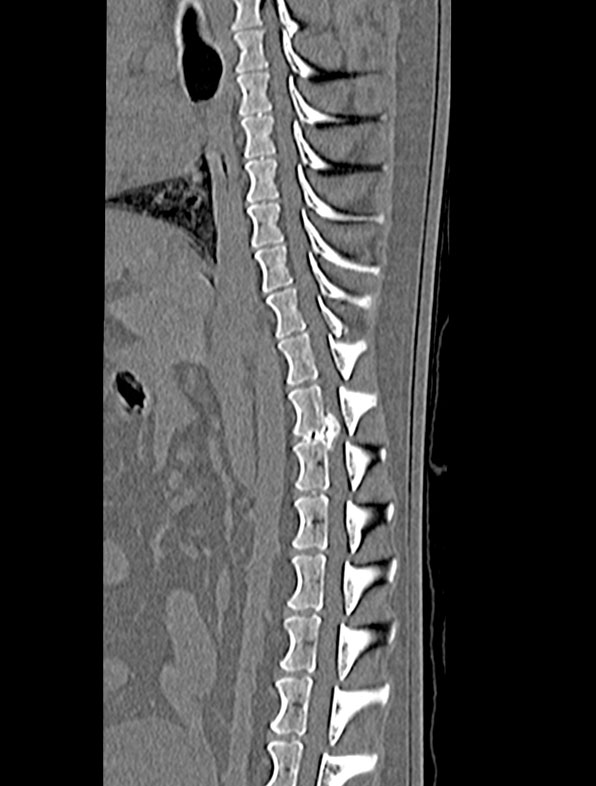

- Lameness/limping or a decrease in weight bearing of one or more limbs

- Dragging one or more limbs

- Inability to walk